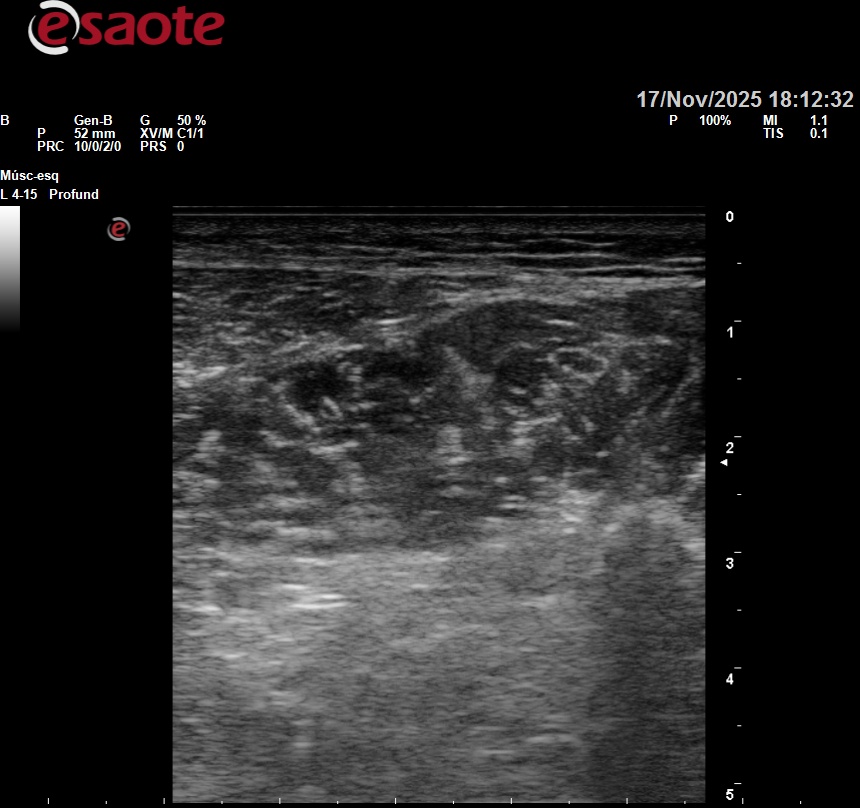

Hallazgos ecográficos

Pérdida de continuidad de fibras musculares en gemelo interno, con área hipoecoica sugestiva de hematoma intramuscular.

La exploración ecográfica permite descartar trombosis venosa profunda y lesiones tendinosas asociadas.